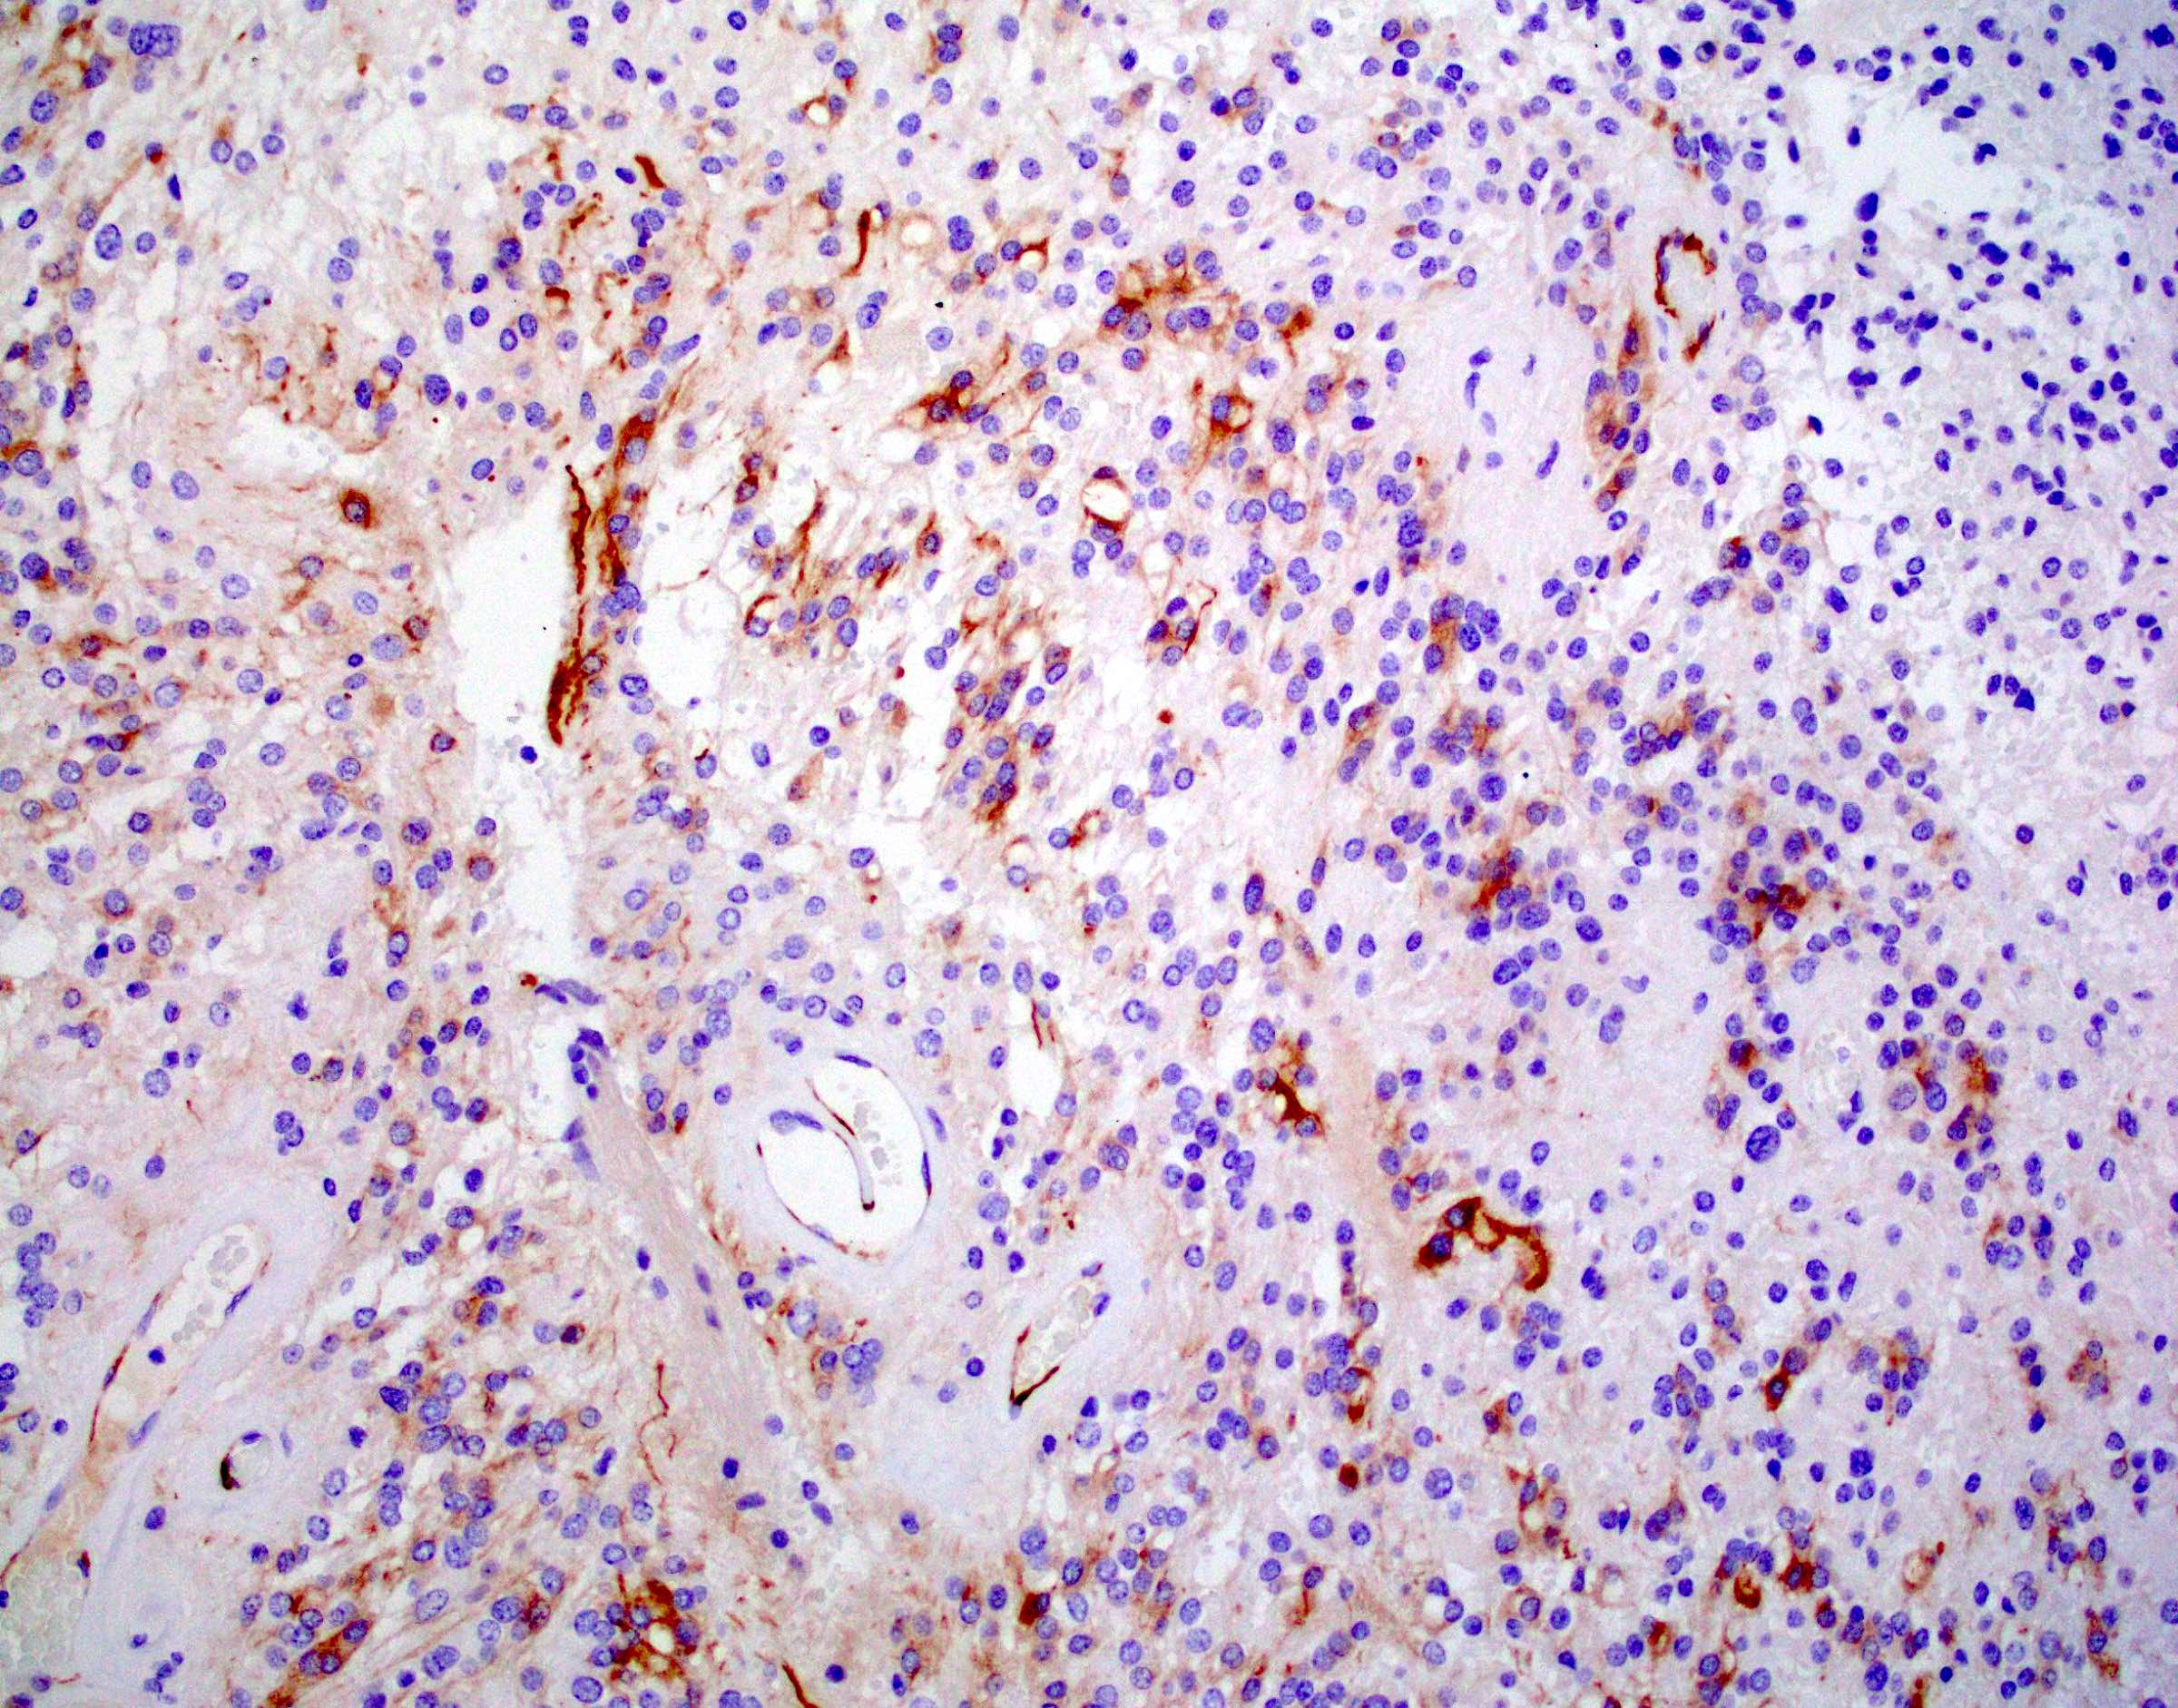

Microscopic (histologic) images

Positive stains

- Positive for S100, GFAP, vimentin

- Perinuclear dot-like pattern of EMA and D2-40 staining

- CD56 staining in lumina and tumor cells